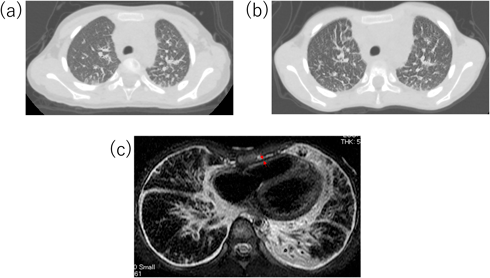

しかし,治療終了後も胸部X線で肺間質陰影の増強が改善せず,発症から3カ月後の胸部単純computed tomography(CT)検査で肺小葉間隔壁の肥厚を認めた(Fig. 2a).本人の自覚症状は特になく,肺線維化マーカーの上昇を認めず,心嚢液再貯留も認めなかったため,外来経過観察を継続した.外来経過観察中,下腿浮腫や肝腫大など右心不全症状は認めず,心臓超音波検査も繰り返し行われたが,心機能は良好で心嚢液の再貯留もなく,拡張障害も明らかでなかった.しかし,胸部X線所見は改善せず,発症後5年頃から徐々に易疲労感を認めるようになったため8歳時に胸部単純CT検査を再検したところ,肺小葉間隔壁の肥厚は悪化していた(Fig. 2b).心筋症の鑑別に心臓MRIを撮像し,心筋の肥厚や菲薄化は認めず遅延造影も陰性で心筋症は否定的であったが,心膜肥厚を認め(Fig. 2c),収縮性心膜炎が鑑別に挙がった.その精査のため,また心筋症の鑑別のため,9歳時に心臓カテーテル検査を行った.その時の圧データをTable 1に,右室圧曲線をFig. 3に示す.右室拡張末期圧の上昇を認めず,右室圧波形もdip and plateau型を示しておらず,収縮性心膜炎も否定的な所見であった.心筋生検も行ったが,錯綜配列などは認めず心筋症も否定された.

Pediatric Cardiology and Cardiac Surgery 42(1): 15-20 (2026)

Fig. 2 Chest CT and cardiac MRI

(a) Chest CT at the age of 3 years shows thickening of the pulmonary lobar interstitial wall. (b) Chest CT at the age of 8 years shows worsened thickening of the pulmonary lobar interstitial wall. (c) Cardiac MRI on T2-weighted black blood method at the age of 8 years shows thickened pericardium. The low-signal area between the arrows indicates the thickened pericardium. CT, computed tomography; MRI, magnetic resonance imaging